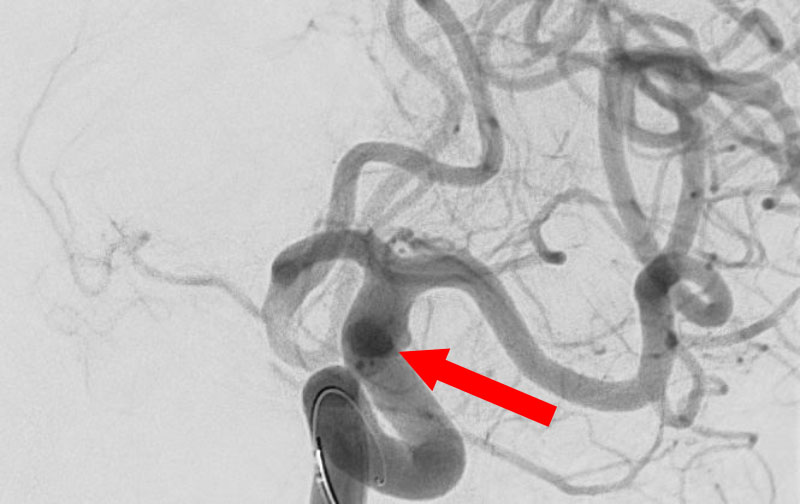

No.1596 手術中